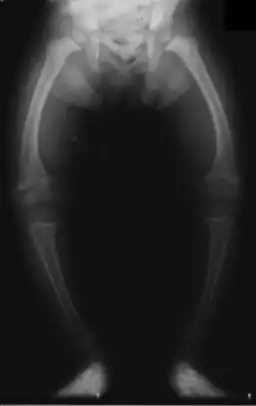

![]() Radiografia unui copil de doi ani ce prezintă deformarea femurului și o densitate osoasă scazută | |